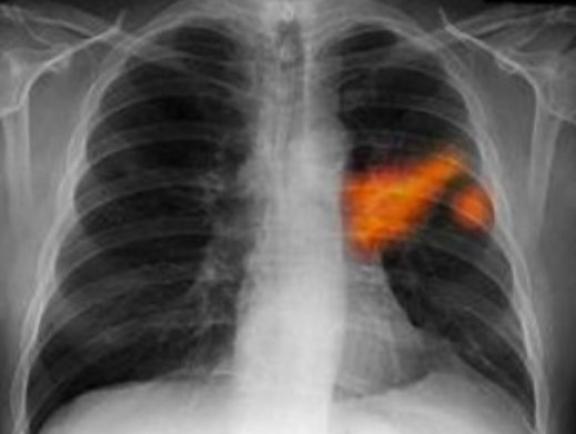

1 Το κάπνισμα: Η πιο κοινή έκθεση στον καπνό προέρχεται από τσιγάρα τον καπνό τον οποίο εισπνέουμε. Έχουν αποδειχτεί οι βλαβερές και καρκινογόνες συνέπειές του εδώ και δεκαετίες.

13 Παθητικό κάπνισμα: Ένας μη καπνιστής είναι 25% πιο πιθανό να εμφανίσει καρκίνο του πνεύμονα αν αναπνέει τον καπνό των άλλων. Αυξάνει επίσης τον κίνδυνο για καρκίνο του λάρυγγα, και του φάρυγγα.